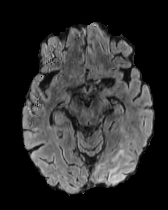

When computing with Eq. (9), the sum of the two components may not produce a perfectly coherent result. However, the incoherence is resolved by the next diffusion step, which fuses the two components better. This would not be the case if we simply computed with DDPM and then applied the mask only at the end of the sampling process. An illustration of this effect is presented in Figure 3, where we can observe how the normal image, generated by applying the mask solely at the conclusion of the sampling process (b), exhibits some artifacts and lacks a seamless transition between the edited and unedited regions.

In Figures 2 and 4 we display examples of healthy images and anomaly maps obtained with the different approaches. We can observe that f-Ano GAN is not able to generate credible counterfactuals and generally produces images of poor quality and unrealistic appearance. On the other hand, the approaches based on diffusion models are able to create more high-quality results. However, the ones obtained with CG and CFG seem to present some artifacts, which may not only impact the realism of the counterfactual examples but also the precision of the anomaly maps obtained from them. In order to better quantify the capability of these methods to accurately segment pathological areas, we compute the Dice scores of the anomaly maps they generate.

In Figure 5 we plot the dice scores obtained for different values of these hyperparameters. As we can observe, we obtain the best performance when employing 500 noising steps and selecting the pixels in the percentile of the saliency maps. In Figure 7 we display counterfactuals obtained with different noise levels. We can observe how smaller values of the noise parameter don’t allow the diffusion model to modify the image to an adequate degree, while bigger values introduce artifacts that impact the image quality of the generated image, consequently also hurting the dice score of the corresponding anomaly map.